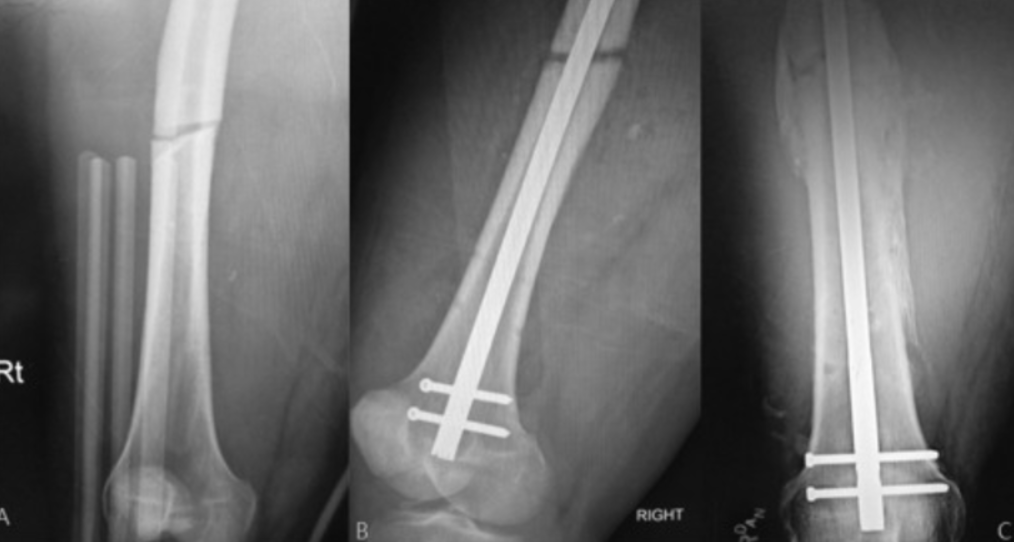

Non-Unions and Revision Trauma Treatment in Pune E...